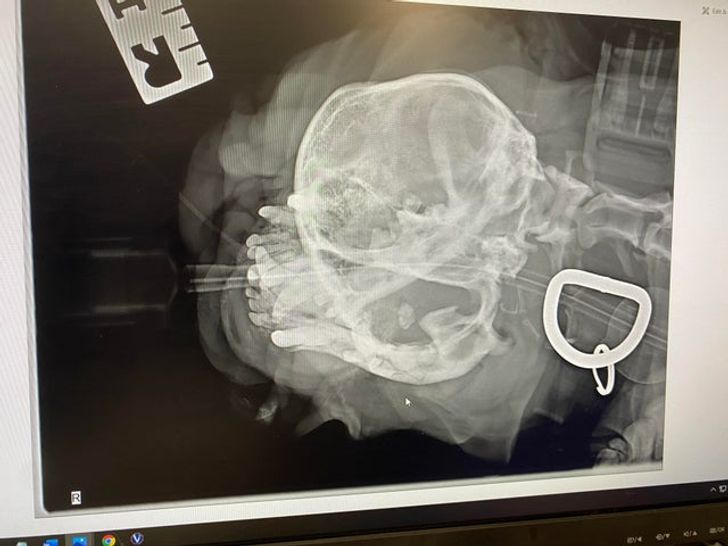

«Мій рентгенівський знімок зубів, зроблений приблизно 2 місяці тому. Дантист отримав від цього справжнє задоволення»